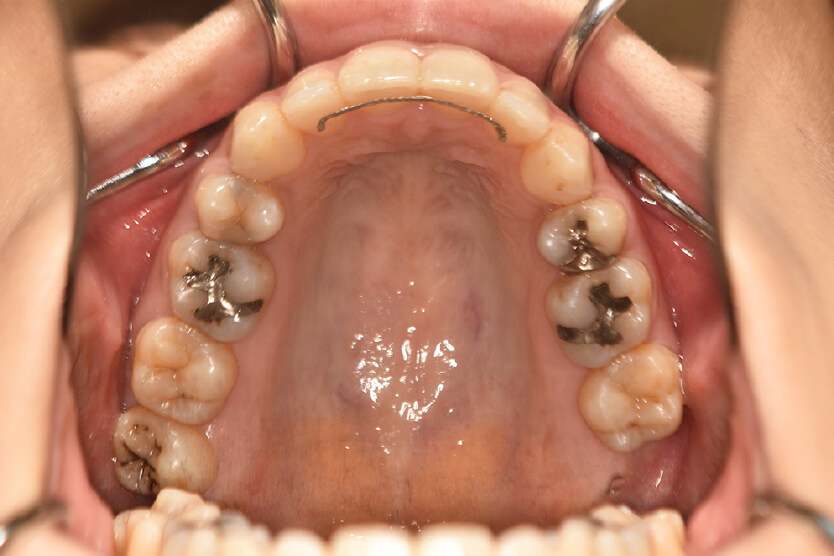

動的治療終了時

症例 症例 症例 症例

治療としては、上顎左右第一小臼歯の抜歯をし、セルフライゲーションブラケット装置(デーモンシステム)とマウスピース型矯正装置(インビザライン)で配列を行いました。

この際、上顎に歯科矯正用アンカースクリューを設置し上顎前歯部後退時の土台としました。

開咬については顎間ゴムの協力もあり改善され、口元も後退し、キレイな横顔になりました。

治療期間は2年4か月でした。